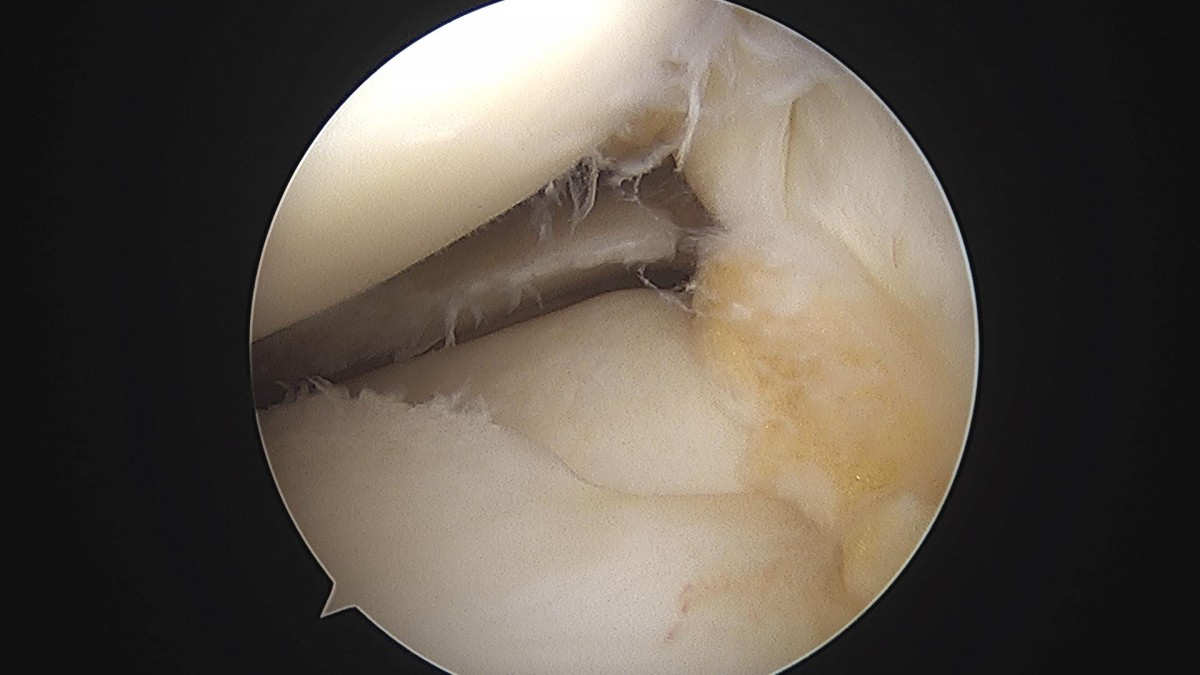

이재상원장님 무릎 반월상연골판 절제술 유지O 환자